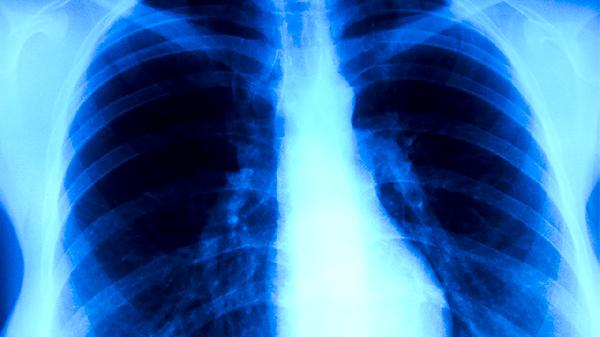

肺結(jié)核的危害主要涉及呼吸系統(tǒng)損害、全身消耗性癥狀、傳染性風(fēng)險(xiǎn)、并發(fā)癥及社會(huì)心理影響。肺結(jié)核是由結(jié)核分枝桿菌感染引起的慢性傳染病,若不及時(shí)規(guī)范治療,可能對(duì)患者健康造成多方面威脅。

肺結(jié)核病灶多發(fā)生于肺組織,可導(dǎo)致肺實(shí)質(zhì)破壞形成空洞,嚴(yán)重時(shí)引起肺纖維化或毀損肺?;颊呖赡艹霈F(xiàn)持續(xù)性咳嗽、咯血、胸痛等癥狀,長(zhǎng)期未治療者可發(fā)展為慢性呼吸衰竭。活動(dòng)性肺結(jié)核患者痰涂片陽(yáng)性時(shí)具有較強(qiáng)傳染性,需隔離治療。